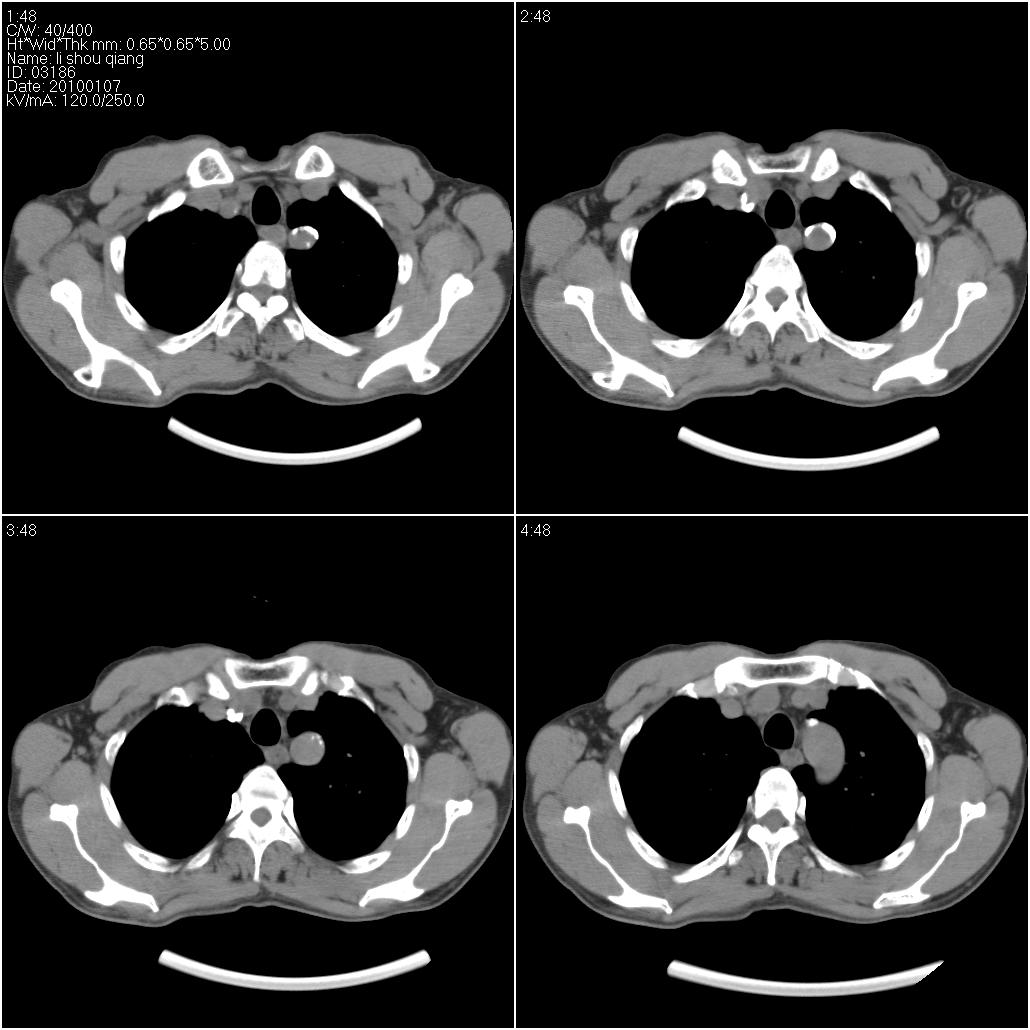

标题: CT24038:男性,58岁。主因咳嗽带血性CT检查。 [打印本页]

标题: CT24038:男性,58岁。主因咳嗽带血性CT检查。

右肺中叶外侧段见一不规则的软组织肿块,边缘可见毛刺,并见厚壁空洞,与胸膜分界欠清。另左下肺见多个小囊状扩张区

右肺中叶外侧段可见团块影,外形不规则,内见空泡征。左下肺见蜂窝状低密度透亮影,部分层面主动脉旁瘤样突出。考虑右肺中叶外围型肺癌可能性大,左下肺支气管扩张,主动脉弓瘤样突出。